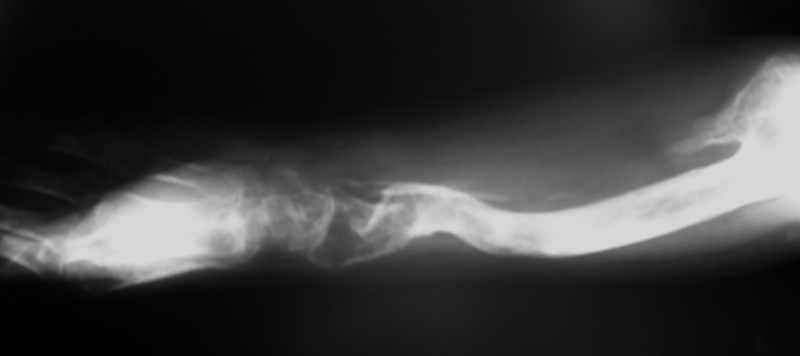

Всем привет!Кому интересно - может лицезреть мое личное наблюдение первичной костной лимфомы с поражением правой большеберцовой кости (см. аттач). Пациент: мужчина, 46 лет. Анамнез прослеживается в течение 1,5 лет - начало заболевания с появления болей.С уважением, Виталий Тазалов.